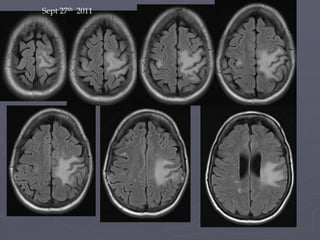

Sept 27th 2011

► 5th July2011 – progression of right sided paresis despite steriods  Commenced Mefloquine (following loading dose) 250mg/week  Mirtazepine 30 gm ► 13th July 2011 - Repeat MRI shows worsening lesion with now definite IRIS

• 63.

13th July 2011(around 6 weeks after Plasmaphoresis – IRIS)